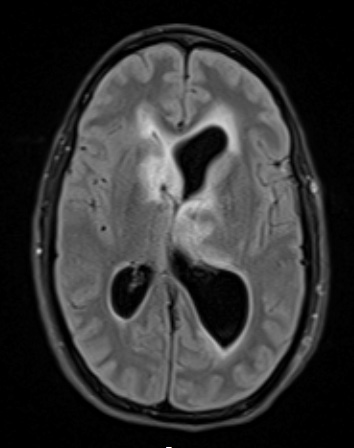

Case 2 History ---- The patient is a 37-year-old woman with a history of Neurofibromatosis type 1 and persistent left optic pathway glioma status post ventriculoperitoneal shunt placement, complicated by obstructive hydrocephalus. There is a separate enhancing area within the right caudate nucleus concerning for glioma. Operative procedure: Left frontal endoscopic septostomy, possible shunt revision with endoscopic biopsy. ---- 2A1 The lesion in the right caudate nucleus is hyperintense on a FLAIR MRI scan.